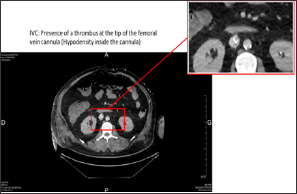

43-year-old patient under noradrenalin was admitted in life-support unit following symptoms of extreme bradycardia associated to 2-minutes low-flow. Initially admitted to the hospital for influenza symptoms with bilateral acute respiratory distress syndrome (ARDS), it appeared rapidly that the patient was indicated for the deployment of an ECMO, which was installed percutaneously between the right femoral vein and jugular vein. At day 12, we observed of a degradation of the respiratory, hemodynamic and renal functions. An increase in the deltaP and the formation of a blood clot indicated a thrombosis of the membrane. The ECMO circuit was completely replaced with a new oxygenation membrane, without changing the cannulas. The patient desaturated very fast during the circuit clamping. Despite the new circuit and oxygenator, a severe refractory hypoxemia persisted conducting to the realization of a thoracic-abdominal-pelvic CT scan (Figure 1), which revealed the presence of a thrombus at the tip of the femoral vein cannula (Figure 2).

Figure 1: Thoracic-abdominal-pelvic CT scan with injection, portal-venous phase, showing the extremity of the femoral vein cannula.